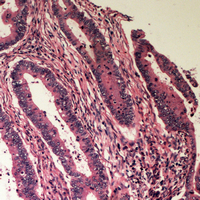

IHC (Immunohiostchemistry)

(Immunohistochemical analysis of B4GALT2 staining in human colon cancer formalin fixed paraffin embedded tissue section. The section was pre-treated using heat mediated antigen retrieval with sodium citrate buffer (pH 6.0). The section was then incubated with the antibody at room temperature and detected using an HRP conjugated compact polymer system. DAB was used as the chromogen. The section was then counterstained with haematoxylin and mounted with DPX.)